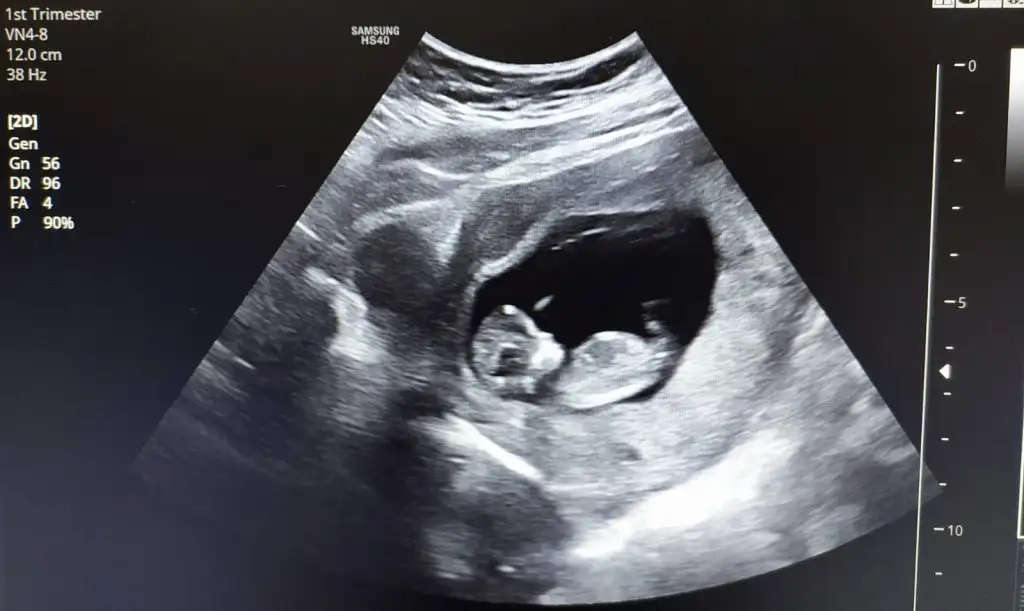

Canım bu ultrasona bakabilir misin belki bir fikrin olabilir 😊 Bu arada 11+5 karından çekildi Pasha22 Pasha22

Eklentiler

• F279E3E8-300A-4D53-A028-266A659A3A33.webp

F279E3E8-300A-4D53-A028-266A659A3A33.webp

18,4 KB · Görüntüleme: 93